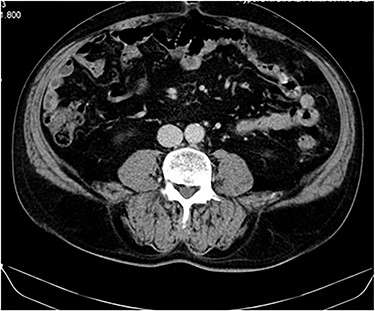

No complications or remission signs were found, lung nodules remained stable and the patient remained asymptomatic (Fig. 3).

CT image at 1-year follow up showing no local tumor recurrence.